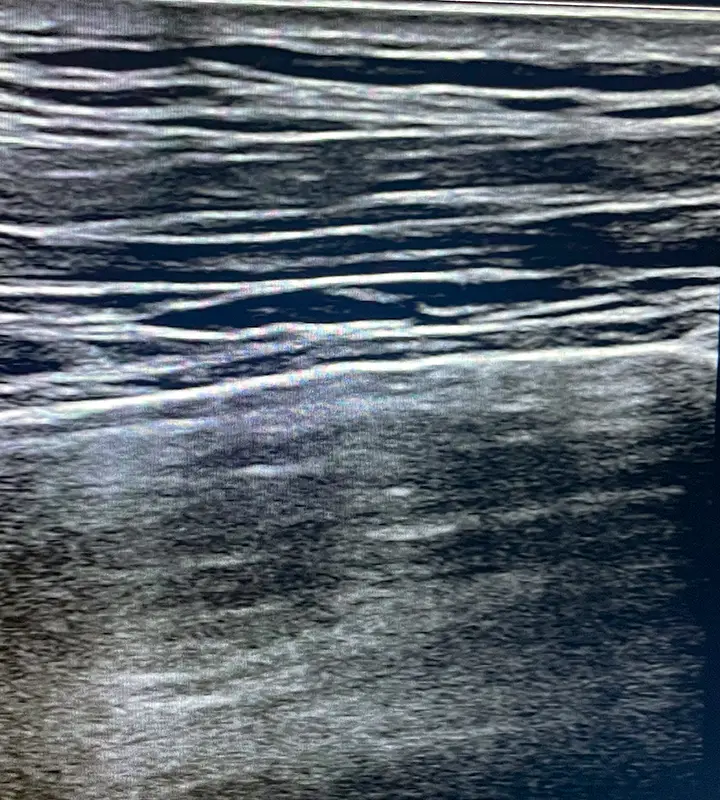

Lungenultraschall

Zur Beurteilung des Volumenstatus und des Therapieansprechens – insbesondere bei akuter oder chronischer Herzinsuffizienz.